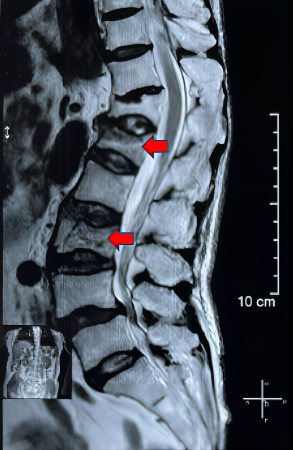

患者术前骨折成像                     患者术后复查结果